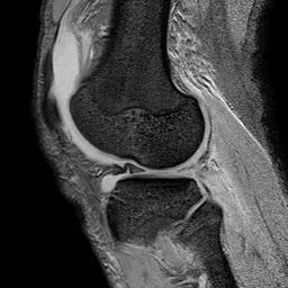

最常见类型:斜行撕裂表现为:在矢状面上见III级高信号到达半月板关节面的上缘或下缘

半月板斜行撕裂